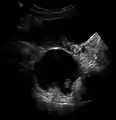

Vaginal and ovarian dermoid cysts

Ovaries normally grow cyst-like structures called follicles each month. Once an egg is released from its follicle during ovulation, follicles typically deflate. Sometimes fluid accumulates inside the follicle, forming a simple (containing only fluid) cyst.[2] The majority of these functional cysts resolve spontaneously.

While all ovarian cysts can range in size from very small to quite large, dermoid cysts are not classified as functional cysts. Dermoid cysts originate from pluripotent germ cells (which are present at birth) that differentiate abnormally, developing characteristics of mature dermal cells. Complications exist, such as torsion (twisting), rupture, and infection, although their incidence is rare. Dermoid ovarian cysts which are larger present complications which might require removal by either laparoscopy or laparotomy (traditional surgery).[3][4] Rarely, a dermoid cyst can develop in the vagina.[5][6][7]